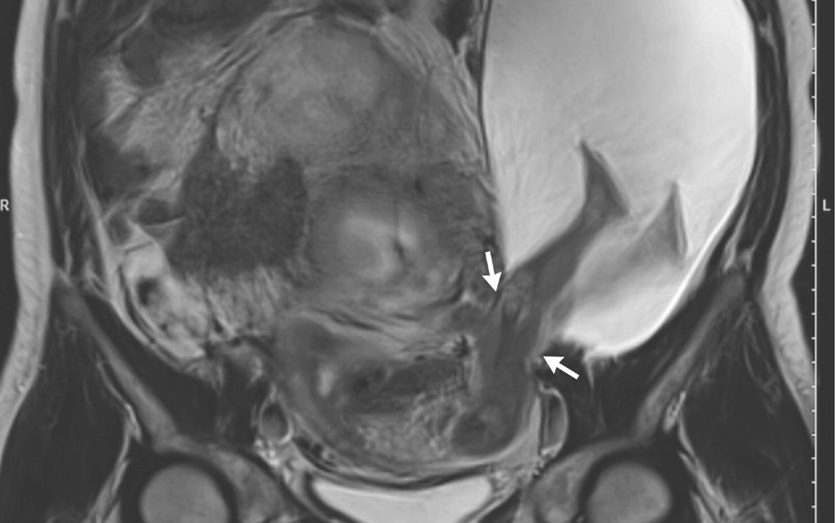

Uma anomalia rara chamou a atenção dos médicos. Uma mulher de 33 anos, que não foi identificada, gerou um bebê com as pernas dele de fora do útero. Ela não apresentava problemas na gestação e caso só foi descoberto após ultrassom.

Segundo o ginecologista do Hospital da Universidade de Angers, na França, Pierre-Emanuel Bouet, na 22º semana de gravidez um corte de 2,5 centímetro abriu no útero da paciente. Bouet disse ao portal Live Science acreditar que isso aconteceu porque esta era a sexta gestação da mulher e as outras cinco anteriores foram finalizadas por cesariana. “Ao que parece, as inúmeras cesárias enfraqueceram a parede do útero da paciente”, explicou.